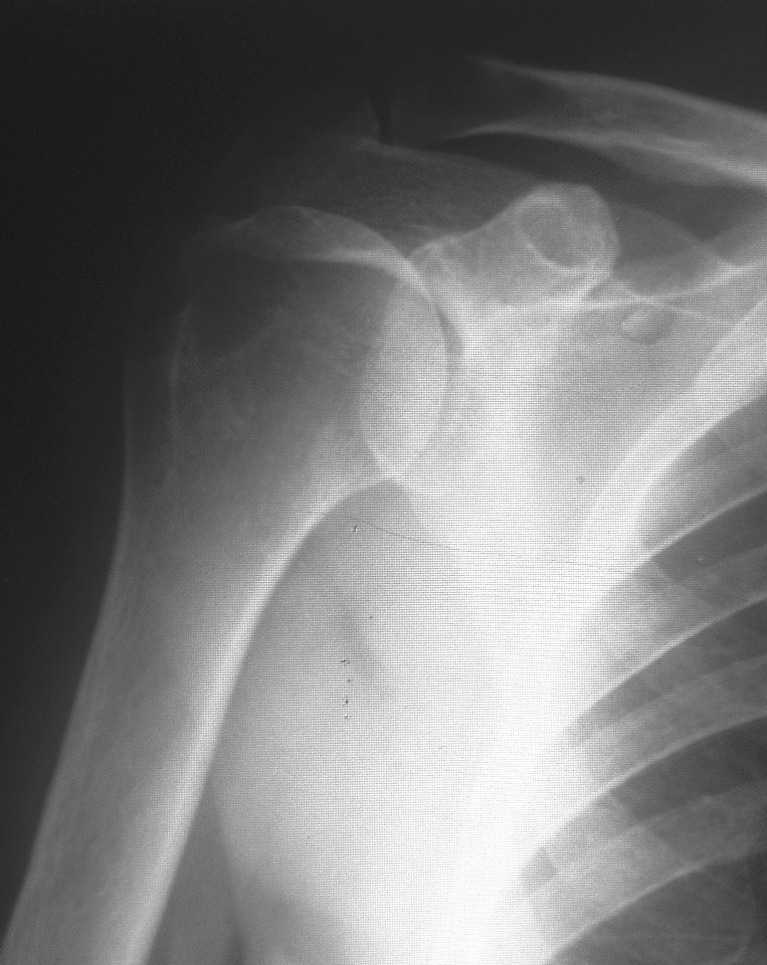

Снимок проводился с целью контроля. Больная обратилась по поводу аналогичного процесса только в левом плече. Я попросил сделать снимок также и правого сустава, так как лечил её в 2003г. с аналогичным диагнозом, но только с правой стороны.

По вашей просьбе размещаю снимок 2003г.

"Меня смущает на представленном снимке "просветление" в области бугра и головки плеча. Или это только мои необоснованные сомнения?"

На первый взгляд непохоже на агрессивный процесс. Возможно, из-за качества снимков, но мне кажется, что на лопатке и на ключице имеются какие то аномальные пятна?

Отсутствие процесса в других участках тела и отсутствие жалоб, наличие характерной локализации, говорит о том, что процесс напоминает ?псевдокисту" головки плеча.

Кроме головки плеча "псевдокиста" встречается еще в передних отделах пяточной кости.

На фоне клинического благополучия, процесс обычно диагностируется в случайных рентген исследованиях.

Из-за отсутствия типичного воспалительного процесса в костномозговой части в Магнето Резонансовых Исследованиях "псевдокиста" показывает нормальный сигнал, поэтому первоочередно необходимо сделать качественные ренген снимки, которые увеличат шансы заметить случайные ?аномальные" находки и установить правильный диагноз.

Конечно, снимки с отведением не помешали бы, но кроме остеопороза у больной других патологических изменений нет